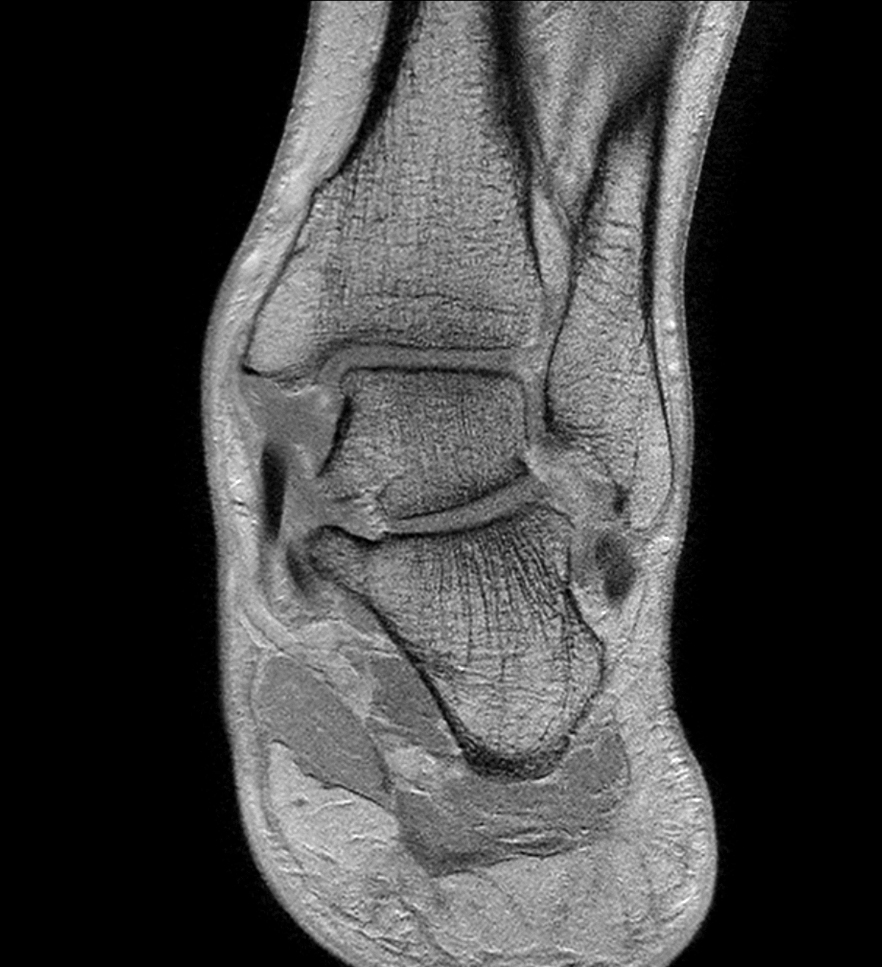

Coronal PDw mDIXON XD TSE (Water only)

-

Coronal PDw mDIXON XD TSE (In Phase)